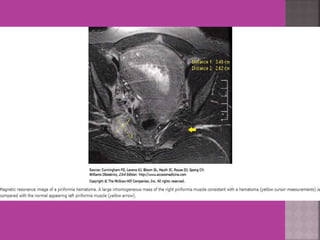

 Study ofnormal uterus and adnexa – with aim to have clear image of normal myometrium, endometrium , ovary and follicles within the ovary.  Myoma—to differentiate myoma from adenomyoma.localization of myoma—sub serous/ intra mural or sub mucous.  Adenomyosis---accurate diagnosis.  Congenital uterovaginal anomalies— bicornuate, septate,subseptate , unicornuate, didelphys ,rudimentary horn and vaginal atrasia etc

 MRI ismost sensitive for diagnosis of Adenomyosis.  MRI Is more accurate and informative in diagnosis of congenital malformation of genito-urinary tract.  Retroparitoneal lymph node > 1cm can be identified so also such small deposits on bowel / bladder liver can be identified in cases of cancers.  It is more sensitive and accurate tool to assess infiltration of myometrial/ cervical wall, adjoining organs and parametrium --thus helps in pre operative staging of genital carcinomas.  As it is safe in pregnancy –it is useful in diagnosis of obstetrical conditions as well s differentiation of tumors (benign / malignant ) complicating pregnancy.